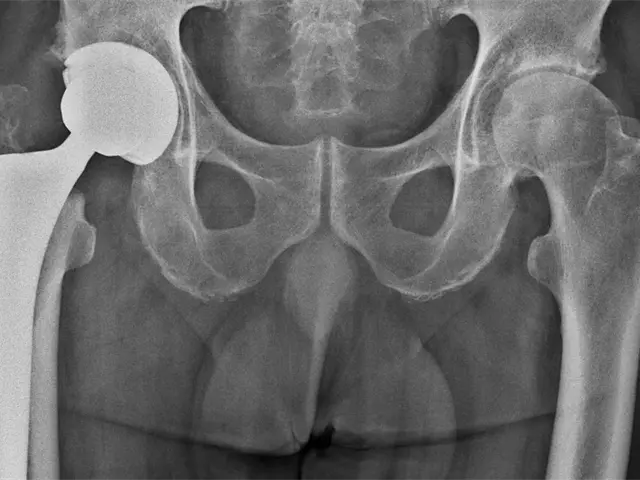

Cirugía inmediata tras fractura de cadera disminuye riesgo de muerte

Ciudad de México.- La fractura de cadera tiene una alta incidencia en personas mayores de 65 años de edad y constituye una de las principales causas de muerte en ese sector de la población.

Se calcula que la mitad de los pacientes muere en los seis meses posteriores a la lesión y gran parte de los sobrevivientes no recupera su nivel previo de independencia y funcionalidad, además de presentar afectaciones en cuanto a su equilibrio físico, mental, funcional y social.

Subrayan que la pronta solución quirúrgica disminuye la mortalidad por fractura de cadera y puntualizan que lo ideal es realizar la cirugía el día de ingreso al hospital o a más tardar un día después, siendo el principal obstáculo para ello la falta de disponibilidad de quirófanos o cirujanos.

También indican que entre más demore la cirugía el riesgo de complicaciones es mayor, siendo las principales: infecciones del tracto urinario, neumonías, tromboembolismo pulmonar, úlceras por presión y otros problemas cardiovasculares.

Los expertos detallan que 95 por ciento de los casos de fractura de cadera en pacientes mayores de 65 años son causados por una caída desde su altura.